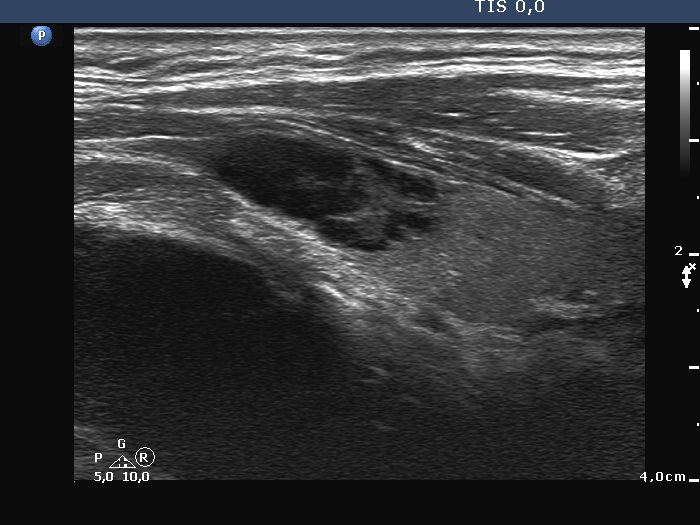

Right lobe, longitudinal scan

Left lobe, another longitudinal scan. Note the hyperechoic lines dorsal to deeply hypoechoic areas.